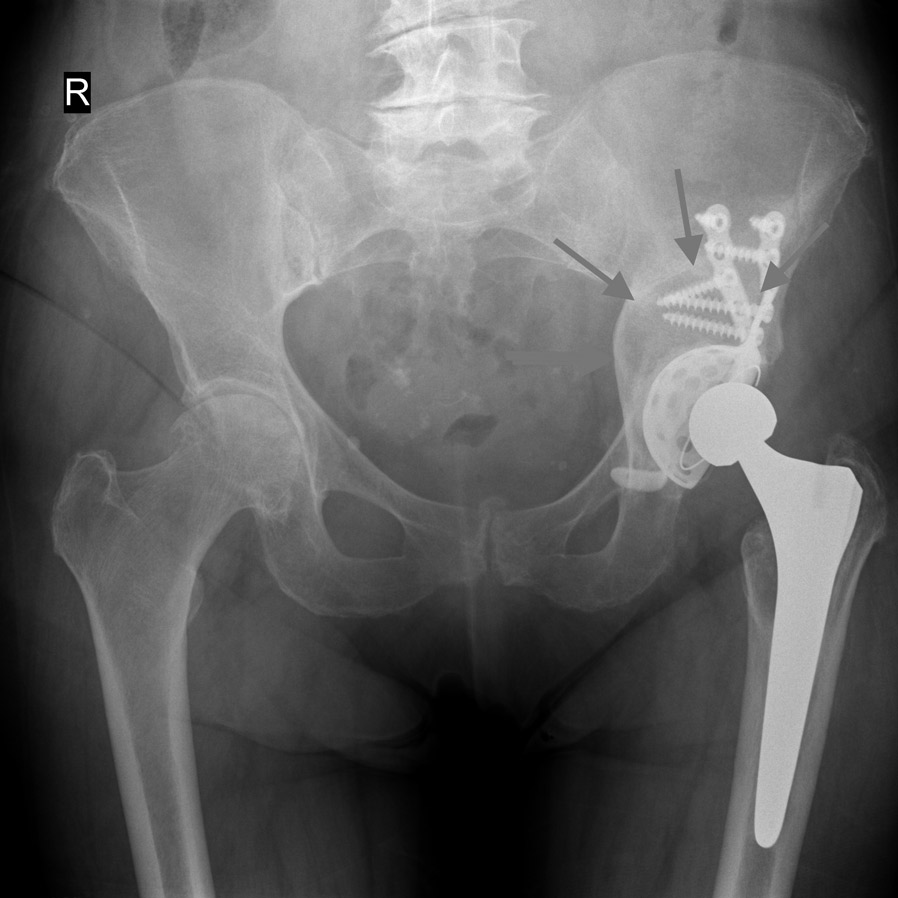

Fig. 2 Completa mobilizzazione con rotazione in senso antiorario e migrazione verso l’alto del cotile (frecce) con ampia usura dell’osso del bacino

Fig. 3 Risultato a 2 anni dell’intervento utilizzando un nuovo cotile con agganci sulla parte di bacino sana. Riempimento del grave difetto osseo del bacino con osso di banca (frecce)